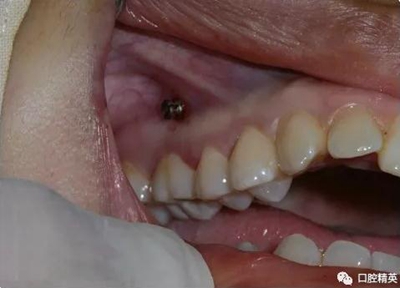

微型種植釘直徑僅有1.6mm和2mm,植入部位幾乎可以不受限制,可植入牙槽骨的任何部位,微型種植體支抗植入手術(shù)操作簡(jiǎn)單、安全,不需要牙齦翻瓣,即可旋入微型種植體,整個(gè)手術(shù)過(guò)程僅需5-10min,術(shù)后患者的不良反應(yīng)少,微型種植體的取出亦非常簡(jiǎn)單,甚至不需局部麻醉,將其反向旋出即可。自攻型種植釘植入牙槽骨中起支抗作用.

再次,植入微型種植體,在附著牙齦處不需要粘骨膜翻瓣,在牙槽黏膜處則需要切開(kāi)黏膜以避免植入時(shí)軟組織被卷入,植入部位通常在膜齦結(jié)合部位或偏根方2~3mm,植入角度與骨面垂直并傾斜15~20度,即向根尖方向植入,術(shù)后拍根尖片以確認(rèn)與牙根的關(guān)系。術(shù)后口服抗生素預(yù)防感染并進(jìn)行口腔衛(wèi)生宣教。

上頜種植釘?shù)闹睆?.6,長(zhǎng)度11mm;下頜直徑2.0,長(zhǎng)度9mm

1、上頜種植釘常見(jiàn)位置在5,6之間;下頜種植釘常見(jiàn)位置在6,7之間。